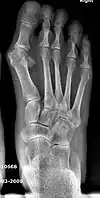

Bunion (hallux valgus) deformity is actually part of a complex of anatomical derangements of protruding mass (bunion), buckling of big toe (hallux valgus) and the bone behind it (metatarsus primus varus), displaced sesamoid bones (detrimental to the important walking function of big toe), collapsed metatarsal arch and several other secondary changes that are the domino effects of metatarsal primus varus. Thus, metatarsus primus varus correction has become the primary objective of all bunion surgeries.

Primus varus deformity

Primus varus deformity is the leaning of the first metatarsal bone away from the second metatarsal and towards the opposite foot (Fig. 1). As it leans over, its head sticks out to form the bunion bump and it also widens the forefoot to cause shoes feeling too tight. Thus when bunion pain becomes unmanageable, surgical correction is to narrow the forefoot by repositioning of the first metatarsal head back to its normal position. This can be done by osteotomy (bone-breaking), soft tissue (non-osteotomy) or fusion techniques.